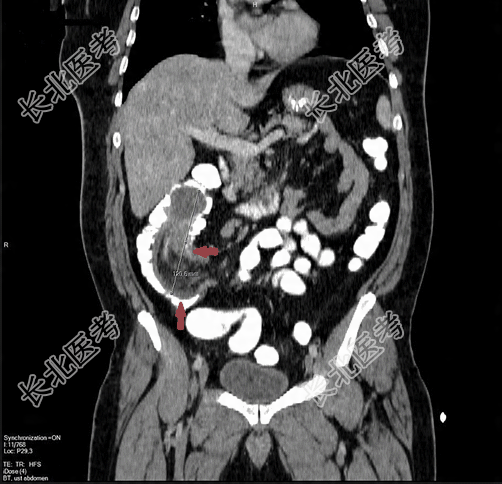

腹部X线平片发现1/2气液平面。进一步腹部CT扫描发现回肠结肠套叠,即外周肠袢低密度,中央为肠系膜脂肪组织。近端软组织密度可见管腔充盈缺损,在小肠袢内发现微小的扩张,直径为3cm,符合肠套叠和肠梗阻的诊断。